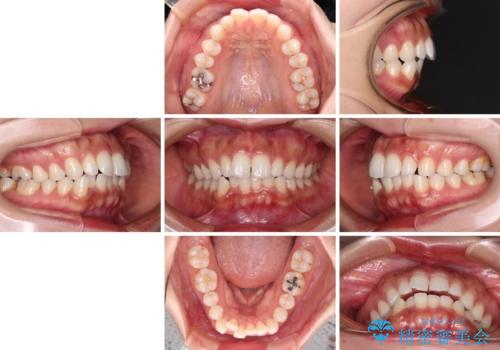

唇が閉じにくい ワイヤー装置での抜歯矯正

- 唇が閉じにくく、上の前歯が下唇に当たって気になるとのことで来院された患者様です。

レントゲン写真での分析結果からは、抜歯矯正をするかどうか悩む境界線上でしたが、主訴が口元の突出感であったため、上下左右の第一小臼歯4本を抜歯して矯正治療を行うこととしました。

上下ともに前歯が少し舌側に傾斜したような仕上がりとなりましたが、口が閉じやすくなったとのことで、患者様には大変満足していただけました。